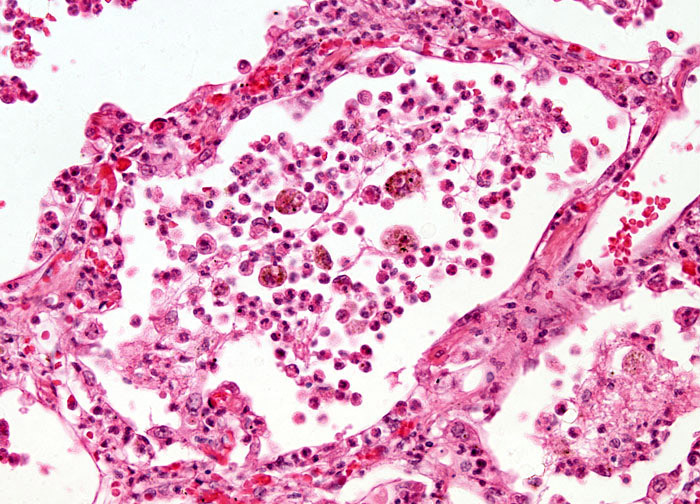

Lobar collapse demystified: the chest radiograph with CT correlation | Postgraduate Medical Journal  Lobar Pneumonia at 20x Magnification | Nikonâs MicroscopyU

Lobar Pneumonia at 20x Magnification | Nikonâs MicroscopyU  Lobar TV - Lobar Incorporated

Lobar Pneumonia, Grey Hepatic Phase Stock Photo - Image of grey, microscope: 130407010  Lobar holoprosencephaly | Radiology Case | Radiopaedia.org

lobar pneumonia - Liberal Dictionary  Lobar hemorrhage | Radiology Reference Article | Radiopaedia.org

Lobar Pneumonia vs Bronchopneumonia | eHealthStar  ENFISEMA LOBAR CONGENITO PDF

Lobar Pneumonia at 10x Magnification | MicroscopyU  Congenital Lobar Emphysema Article